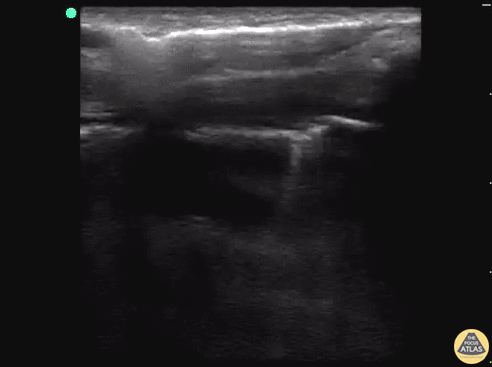

Another example of lung point from the POCUS Atlas Trauma section. Lung point indicates the transition point between normal pleura with normal lung sliding (on the left side of the image) and where there is air disrupting the pleural space with decreased lung sliding (on the right side of the image). Lung point is a highly specific finding indicating a pneumothorax. Dr. Sathya Subramaniam, Pediatric EM Fellow - Kings County/SUNY Downstate